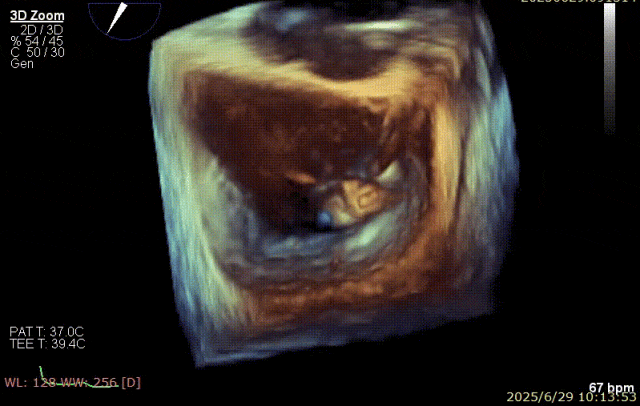

2025 年 6 月 29 日,经过对术前超声和 CT 影像进行深入分析,团队制定了周密手术计划。在麻醉手术中心副护士长刘菊梅的充分术前准备和中国医学科学院阜外医院欧阳文斌教授的指导下,凭借团队的紧密协作和娴熟操作,单纯利用超声影像精确引导,通过导引导管系统经右胸、右房,穿房间隔,建立到达左房通路;经该通路将两枚二尖瓣钳夹成功植入二尖瓣病变部位进行夹持,夹合器位于 3 区及部分 2 区,固定好,运动协调,瓣叶启闭灵活,瓣口轻度反流,二尖瓣平均跨瓣压差 2 mmHg。手术圆满完成。

器械植入后二尖瓣 AP 径约 35 mm,CC 径约 39 mm;夹合器固定好、组织桥稳定,前瓣夹闭后瓣叶长度 25 mm,后瓣夹闭后瓣叶长度 7 mm;二尖瓣开放好,瓣口呈大小双孔,二尖瓣瓣口面积约 2.8 cm²,平均压差 1 mmHg,关闭可,二尖瓣反流明显减轻(从术前反流 4+显著改善至 1+),手术全程无需体外循环支持,无需输血,无需射线全超声引导。患者术后第二日回普通病房,患者恢复良好,术后第五日即出院。

郑宝石教授介绍,经右胸小切口穿房间隔介入二尖瓣缘对缘钳夹治疗二尖瓣反流优势在于该入路减少过弯,对输送系统部件性能要求较低,手术路径短,钳夹调节简单准确且房间隔穿刺高度要求低于经股 TEER。另外,手术在全超声引导下完成,安全无射线危害;术前 3D 重建可在体外准确模拟手术路径。